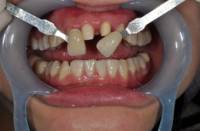

☞准备工具:单反相机、环形闪光灯、微距镜头85mm以上、张口器、黑色板、反光板、比色板

比色板与牙齿保持于同一水平线